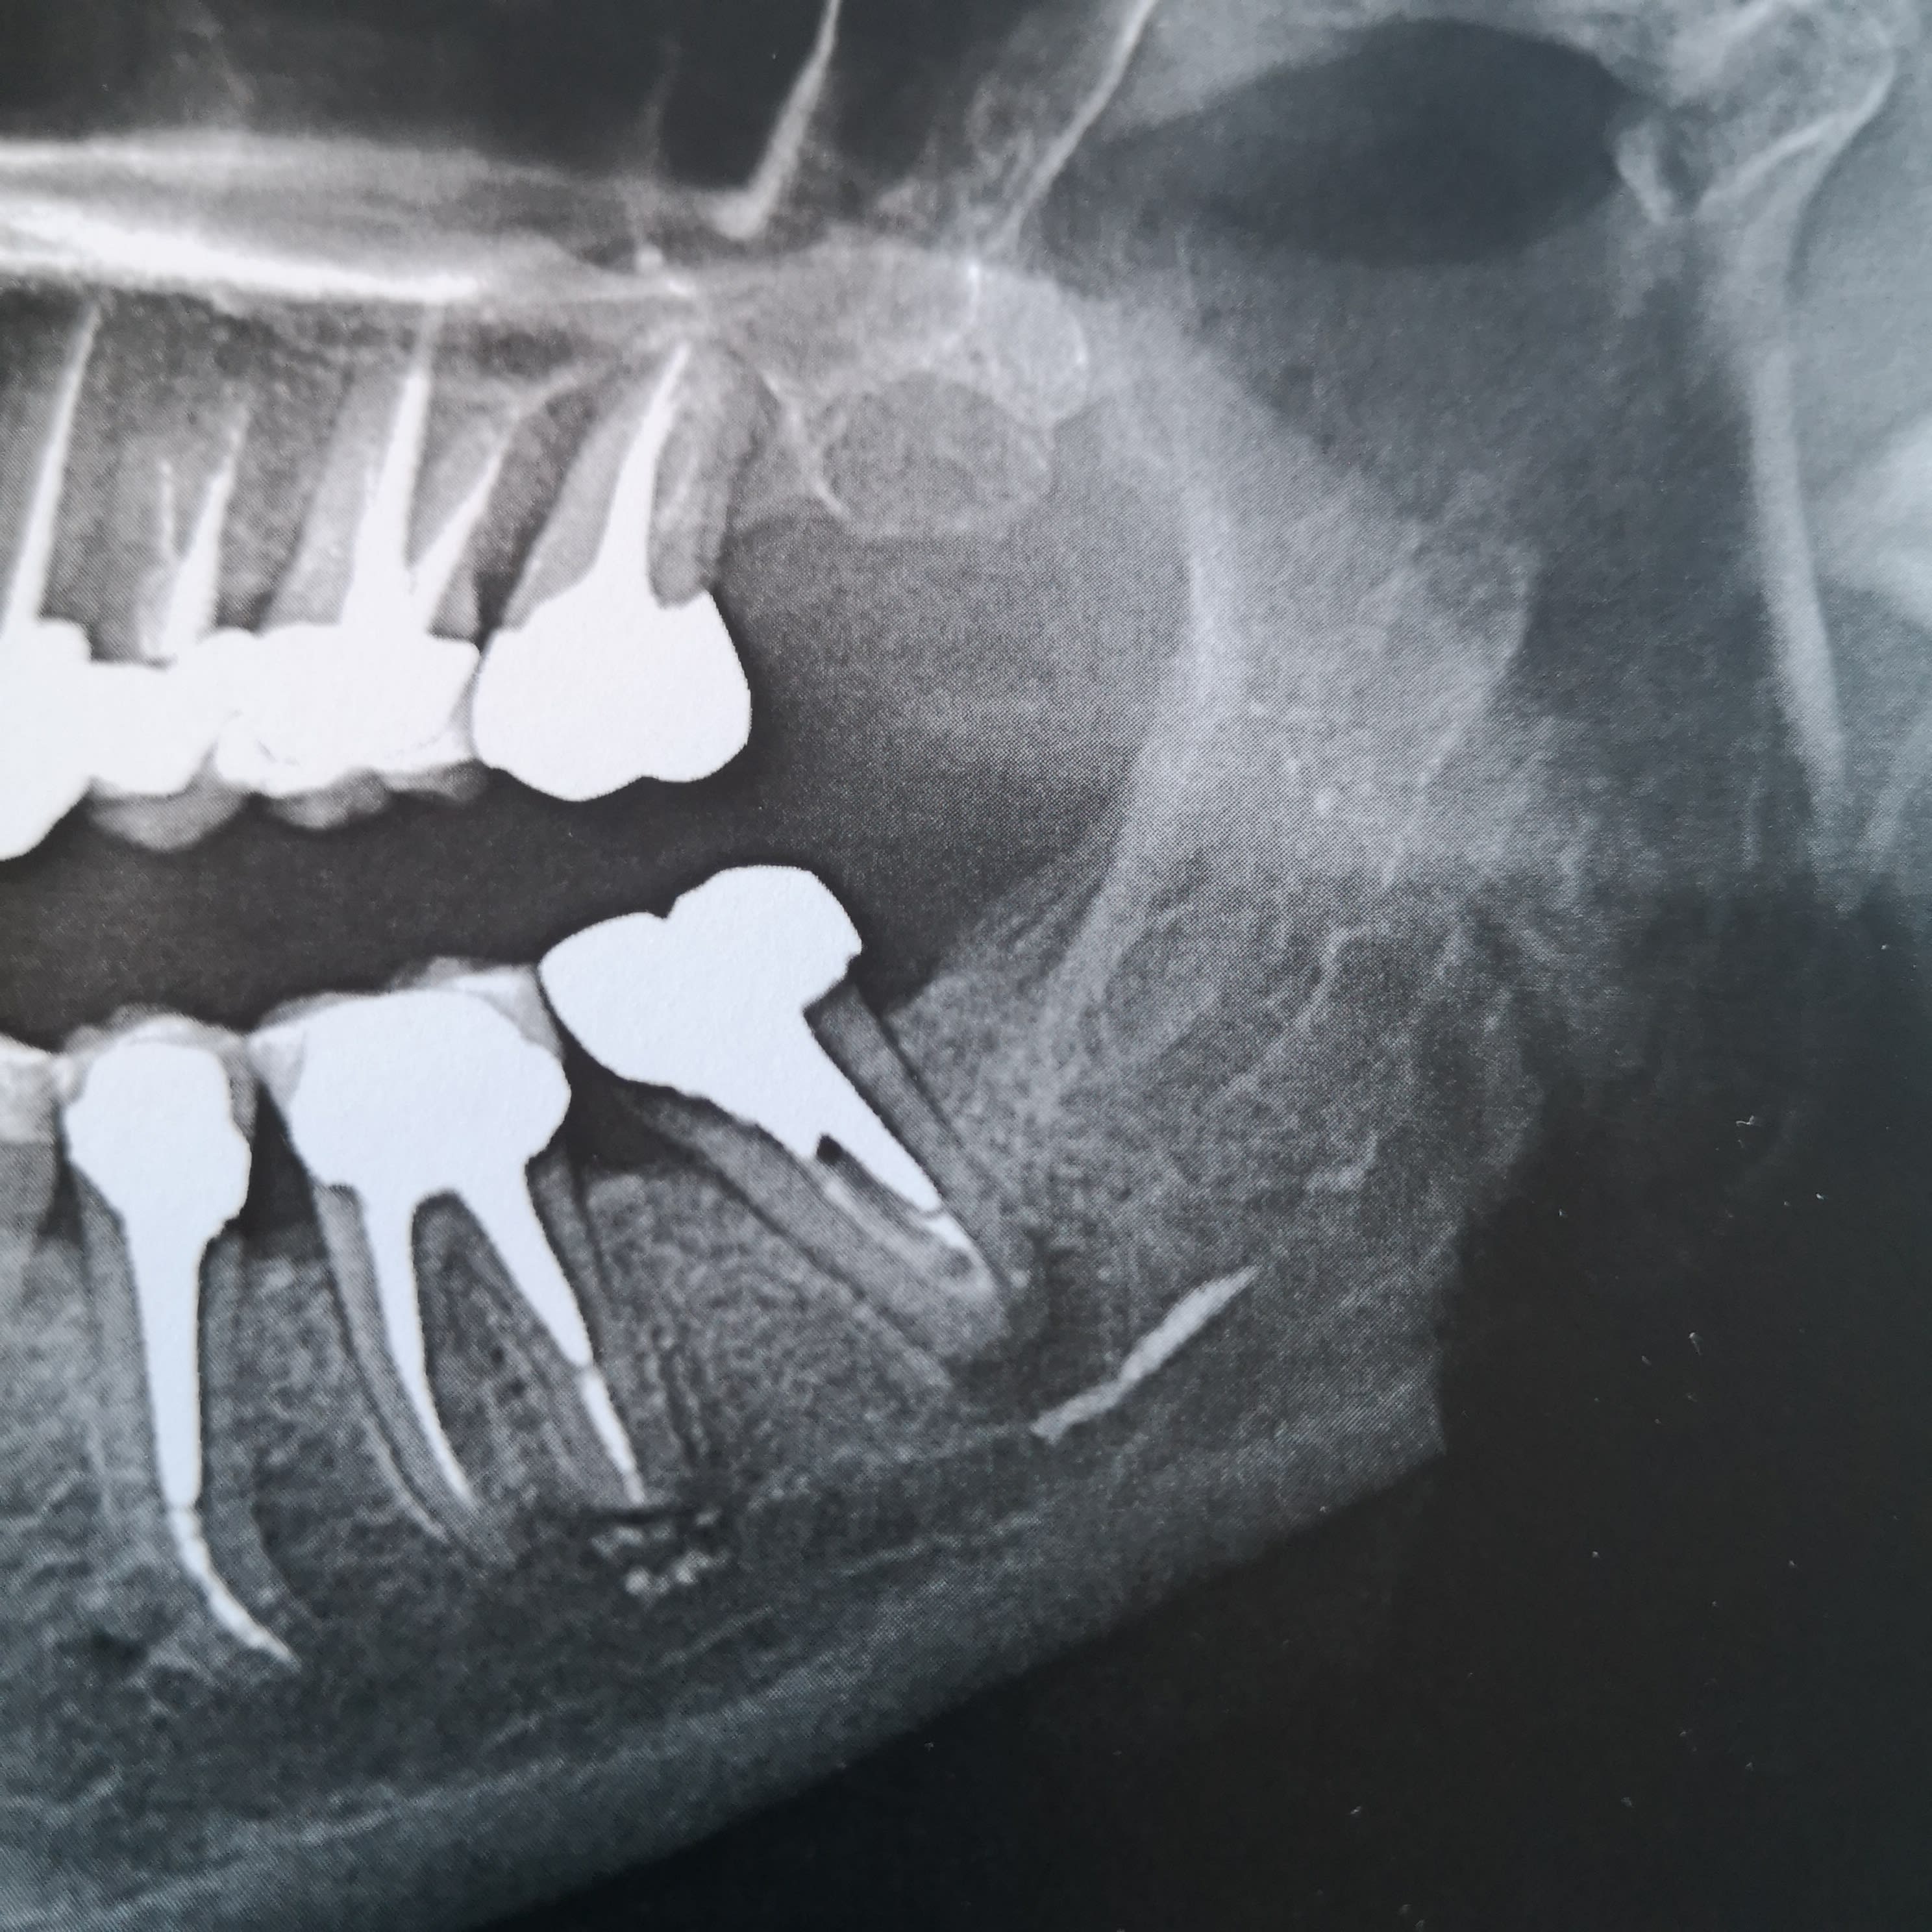

je vous tiens au courant de mon cas pour ma 37 en ERI. Belle diminution de la lésion, le seul truc c'est que le patient perd patience ...alors décision: je m'en ressers pour pilier de bridge ou pas ?

je vous joins les cones beam de juin 2019 avec la lésion initiale et celui d'aujourd'hui.

la première 3D date de juin 2019